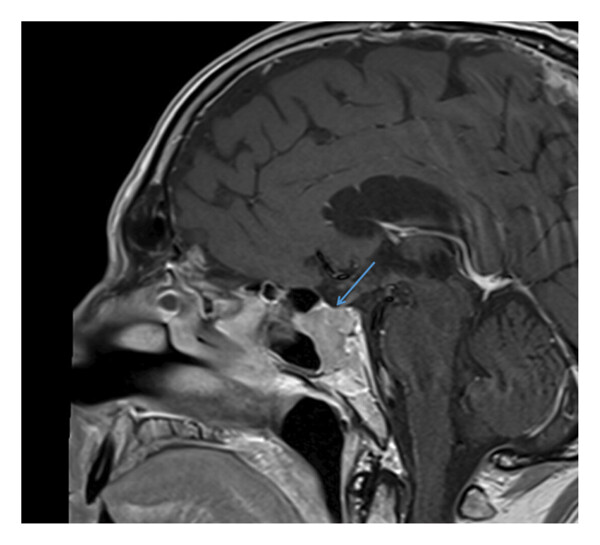

Дифференциальный диагноз включал аденому гипофиза, хордому или метастатическое поражение. С этой целью у пациента был исследован гормональный профиль (без отклонений) и проведено офтальмологическое обследование (без отклонений). КТ грудной клетки, брюшной полости и таза также не выявила злокачественных новообразований. Повторная МРТ выявила вестибулярную шванному справа размером 1,6 см и подтвердила наличие образования в передней части турецкого седла (рис. 2).

Рисунок 2. МРТ-снимок в аксиальной плоскости после введения контрастного вещества. Синяя стрелка указывает на правостороннюю вестибулярную шванному с внутриканальными и цистернальными компонентами. Значительное объемное воздействие на ствол головного мозга или среднюю ножку мозжечка не выявлено.